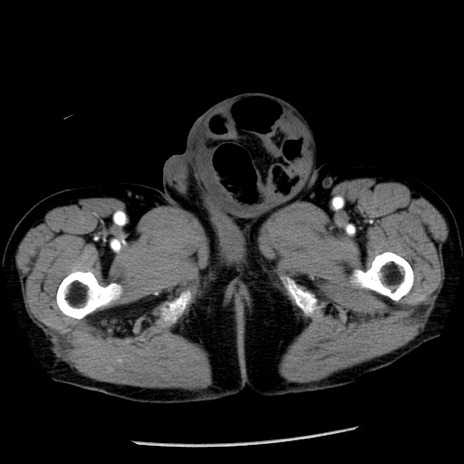

症例26(横断像)

【症例】80歳代男性

【主訴】嘔吐

【現病歴】昨晩2回嘔吐あり、今朝になっても嘔吐あり。来院。

【既往歴】胃潰瘍

【身体所見】意識清明、BT 37.6℃、BP 166/95mmHg、HR 100bpm、SpO2 97%、腹部:平坦・軟、腸蠕動音聴取良好、圧痛なし。

【データ】WBC 21900、CRP 1.46